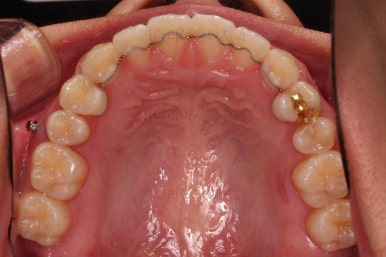

윗니의 배열과 위치는 거의 완성이 되었고요.

아래는 아직 틈이 많이 보이죠.

어금니를 부산치아교정 통해 계속 앞으로 당겨줍니다.

아랫니 틈은 거의 없어졌네요.

대신 여러 교합적인 이유로 아랫니를 좀 더 앞으로 당겨주긴 해야 합니다.

이제 마무리를 해봅니다.

교합 양호하고 치아 사이 틈새도 잘 모아졌습니다.